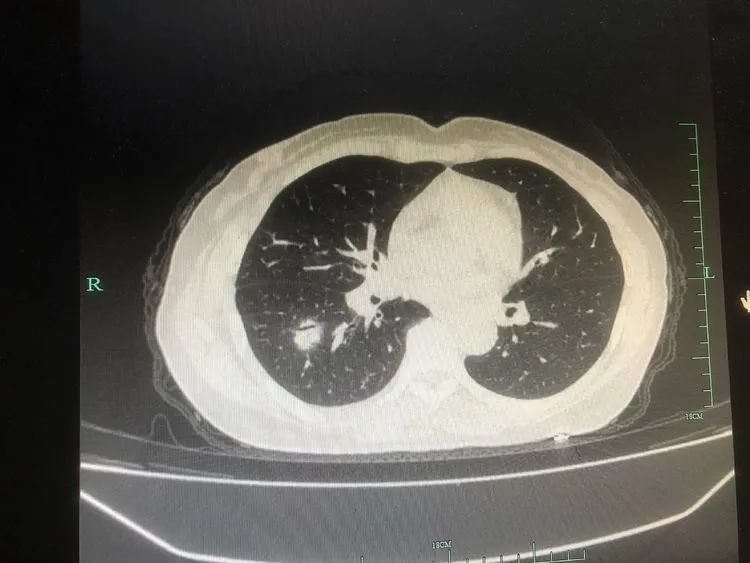

患者,楊某某,中年女性,既往有“風(fēng)濕性關(guān)節(jié)炎”病史,此次因“發(fā)熱、咳嗽2天”于2021-12-12晚入住我科;入院胸部CT提示右肺下葉結(jié)節(jié)影及大片實(shí)變影。